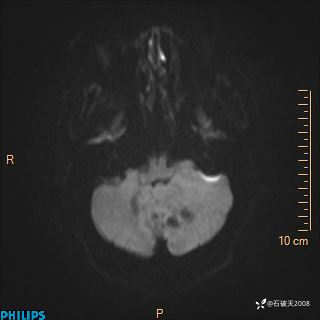

DWI